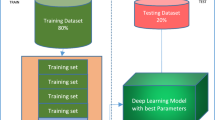

COVID-19 has become the global epidemic affecting millions of people across the world. The fact that COVID-19 spreads quickly and devastating for elderly person makes this disease lethal as we witnessed a massive mortality rate in first, second, and third wave since 2020. Early diagnosis of COVID-19 is mandatory to prevent the spread and damage control, as only few nations have been able to vaccinate more than 50% of their population. The healthcare professionals commonly use the real-time polymerase chain reaction (RT-PCR) test to identify the COVID-19. Although RT-PCR test is considered more reliable among other COVID-19 detection tests; however, sensitivity of RT-PCR lies in the range of 65%-95% and took hours to diagnose the COVID-19 disease. Therefore, there exists an urgent need to develop more rapid and reliable diagnostics methods for COVID-19. In this regard, Chest X-ray and CT scan images are also being used to determine the abnormalities in the lungs of the COVID-19 patients which are found after the initial symptoms of this disease. We exploit the benefits of convolution neural network (CNN) for reliable detection of various diseases and used it for COVID-19 detection. For this purpose, we proposed a deep learning model to automatically detect the COVID-19 disease by processing the chest X-ray images. More specifically, we presented an Inception-ResNetV2 network-based deep learning model for COVID-19 detection. Performance of our model is evaluated on the publicly available COVID-19 dataset. The accuracy of 96% indicates the effectiveness of the proposed model for COVID-19 detection.